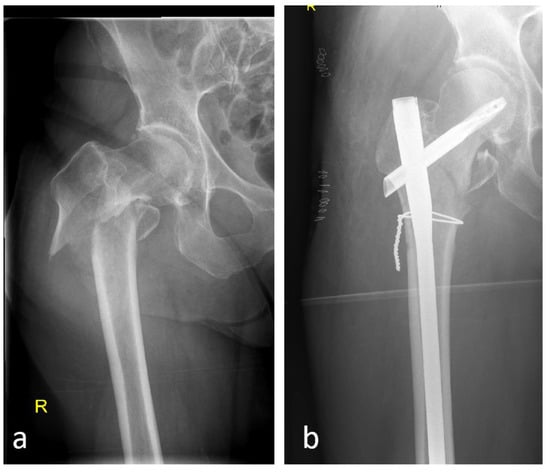

5.2. Open vs. Closed Procedure

- Sharma, G.; GNK kumar Yadav, S.; Lakhotia, D.; Singh, R.; Gamanagatti, S.; Sharma, V. Pertrochanteric fractures (AO/OTA 31-A1 and A2) not amenable to closed reduction: Causes of irreducibility. Injury 2014, 45, 1950–1957. [Google Scholar] [CrossRef]